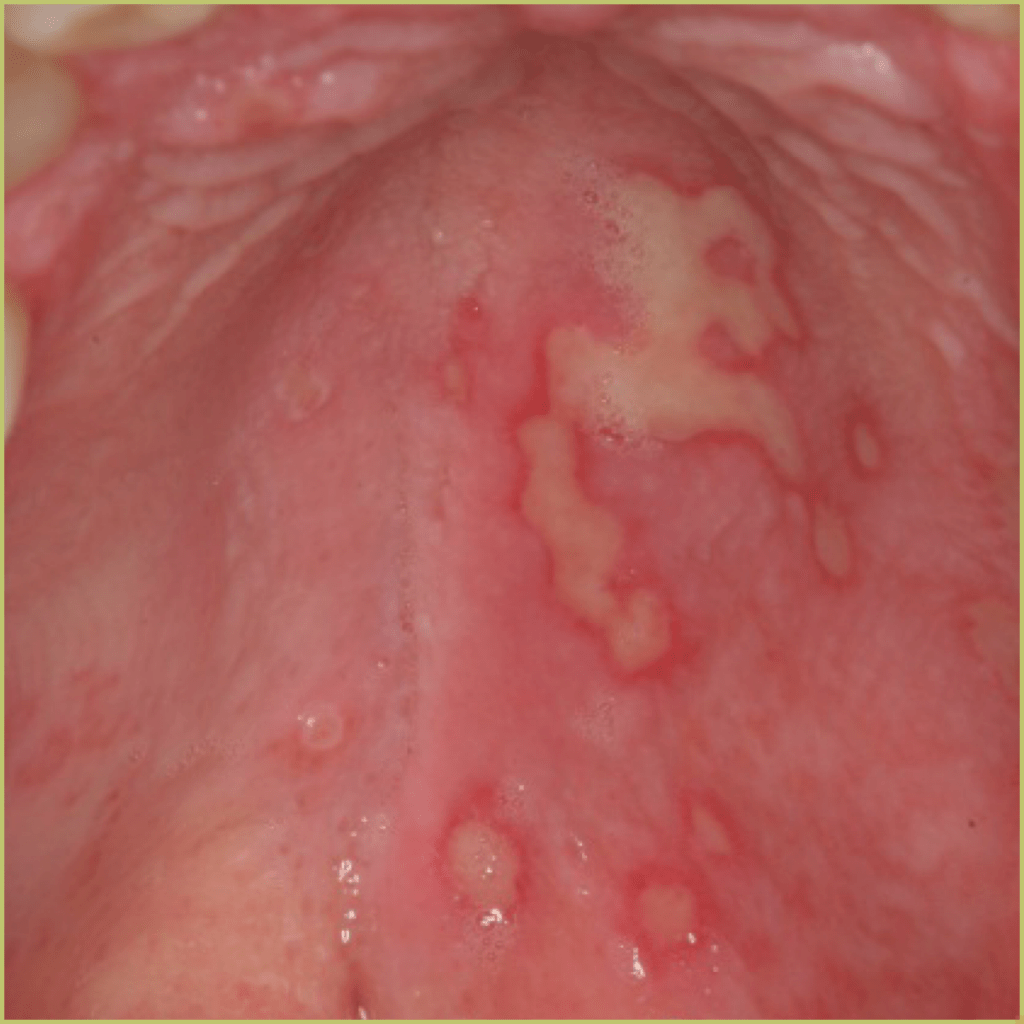

HAND FOOT and MOUTH

Hand-Foot-and-Mouth Disease is a very common childhood disease caused by an enterovirus (coxsackievirus A and B) infection. It is principally seen in children under 5 years of age. The common clinical presentation includes:

- Incubation period of 5 to 9 days, resolves in about a week.

- Oral mucosal lesions that are similar to those resulting from herpes simplex infection.

- Non-pruritic and painless maculo-papular eruption on the hands, feet, and mouth.

- Palmar, plantar, and digital lesions are vesicular and erythematous.

- Usually involves nonkeratinized mucosa (soft palate, floor of mouth, buccal mucosa).

- Symptoms are usually mild.

- Resolution occurs without scab formation and does not lead to scarring.

Diagnosis is usually based on the lesion history and clinical presentation only. Your differential diagnosis should include:

- Herpangina.

- Herpes simplex infection.

- Lymphonodular pharyngitis.

The disease is self-limiting and treatment is usually palliative only.